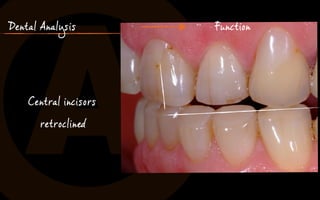

Dental Analysis Function

no tender muscles, no joint problems

Central incisors

retroclined